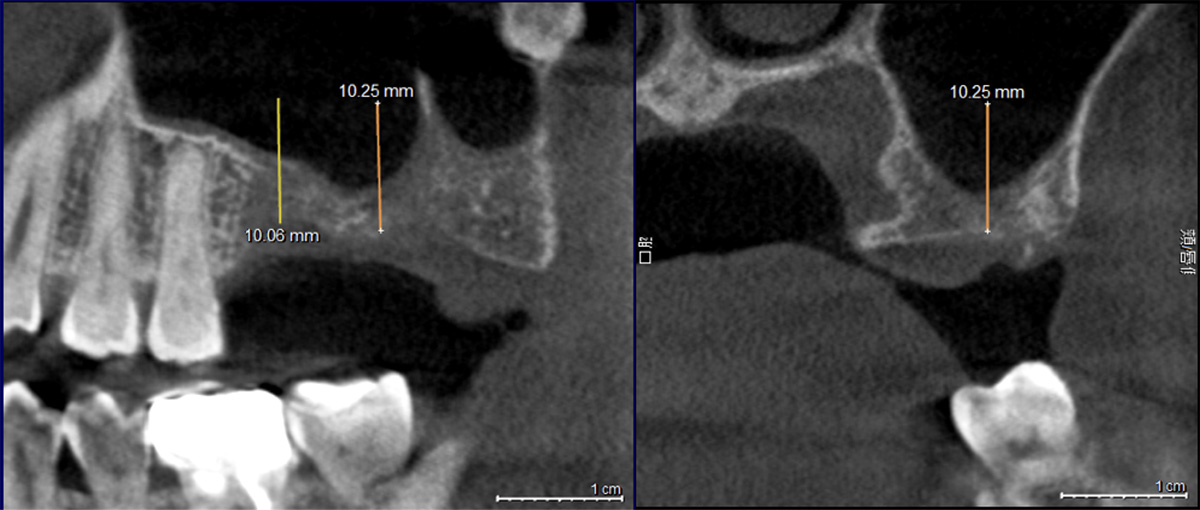

【サイナスリフト前レントゲン写真】

黒く写っている部分は上顎洞と呼ばれる空洞で、インプラントを支えるための骨が不足している状態です。

このままインプラントを埋入すると、十分な初期固定が得られず、将来的な脱落やトラブルのリスクが高くなります。